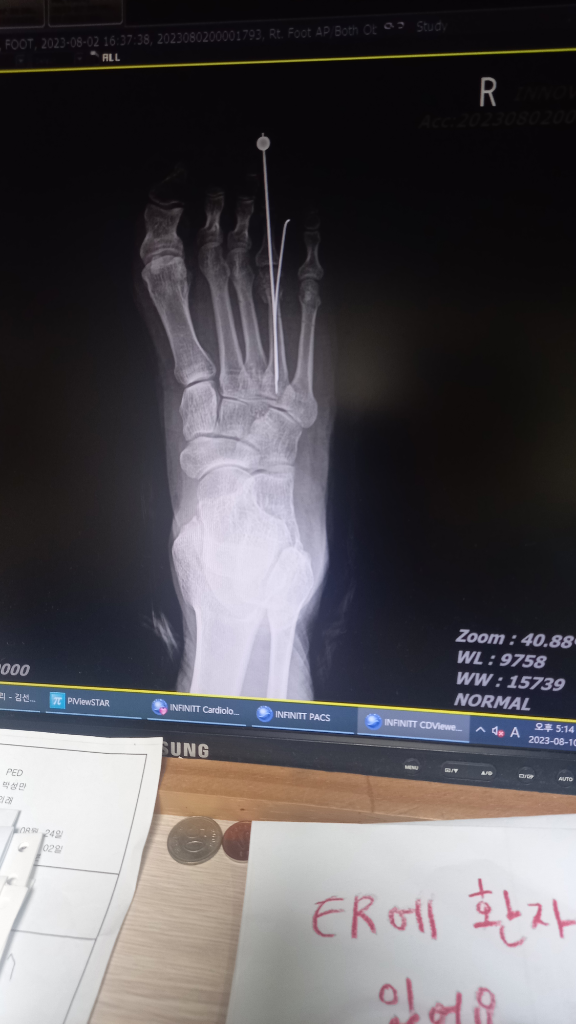

발쪽에 뼈가손상이되서 수술하고

6주간의진단이나왔음니다 그리고 택시기사도

6주가되는날병원에 핀제거하러오라는데